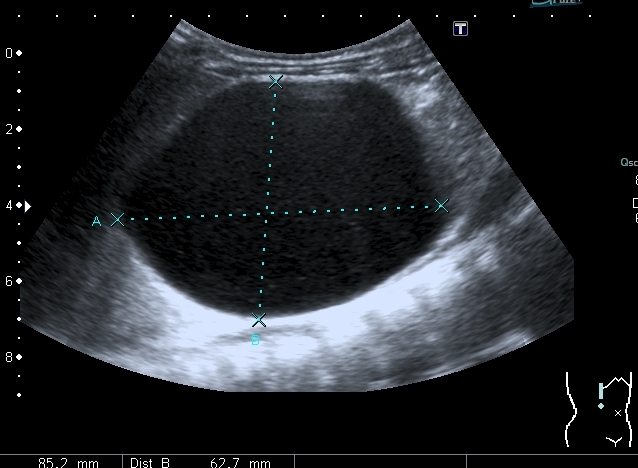

Ещё картинки гидронефроза у ребёнка 6 - ти месяцев, спутать такой гидронефрозище с синусной кистой сложно, а вот с кистой брюшной полости - запросто

Сканирование высокочастотным датчиком  - резидуальная паренхима